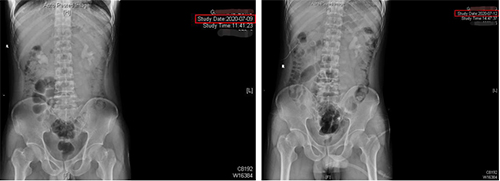

“经皮肾镜取石术”术前、术后X片对比

“铸型结石”患者高某某:

这三位患者均患有“铸型结石”,陈修德主任医师和陈少安主治医师均予以采取“一期、单通道经皮肾镜取石术”,取石完全,其中一位患者留置肾造瘘管,术后5天出院;其余两位患者未留置造瘘管,术后3天出院。